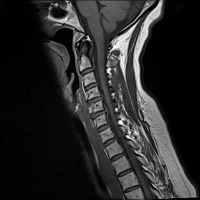

Classes (24)

Annular Disc Relaxationrotation

Annular Tearrotation

Annular disc relaxationrotation

Annular tearrotation

Degenerated discrotation

Degenerative Disc Diseaserotation

Demyelinating Plaquesrotation

Demyelinating plaquesrotation

Disc Bulgerotation

Disc Bulgerotationtrack_idkeyframe

Disc Herniationrotation

Disc Protrusionrotation

Disc Relaxationrotation

Disc bulgerotation

Disc bulgerotationtrack_idkeyframe

Disc herniationrotation

Disc protrusionrotation

Disc relaxationrotation

Fracturerotation

Hemangiomatarotation

Osteophytesrotation

annular tearrotation

diffuse disc bulge with neural compromiserotation

stenosisrotation